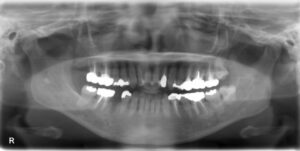

下顎臼歯5本欠損症例

BEFORE AFTER 61歳女性/下5本欠損/インプラント埋込手術 【治療内容】 右下は第一小臼歯と第一大臼歯を繋ぐ…